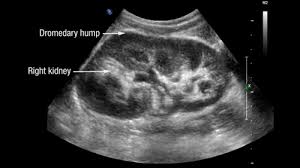

Dromedary hump appears as a focal bulge on the lateral border of the left kidney, caused by molding of the normal renal parenchyma by the adjacent spleen.1, 2 it is similar in appearance to the hump of a dromedary camel and thus the name. A dromedary and its child, two hours old. Apart from the differences in the number of humps, there are other notable differences too. Hello, i'm marcelo from brazil. Bactrian camels have two humps, while the dromedary camels have only one hump on their back.

Dromedary hump appears as a focal bulge on the lateral border of the left kidney, caused by molding of the normal renal parenchyma by the adjacent spleen. A dromedary has one hump, long limbs and short hair. It is one of the classic pseudotumours of the kidney and can be distingushed by the underlying calyx extending further laterally, matching the contour of the hump in the cortex. Dromedary hump and bertini columns are two of the renal pseudotumors. Dromedary camels live in hot climates. = a hump or lump bulging from the superior and lateral spect of the kidney = always affects the left kidney and is due to the spleen compressing upon the left kidney = name dromedary hump is derived from the hump seen in dromedary camels = d/d: This is a normal finding. Since this looks like camel's hump on the film, this is called dromedary hump. Care should be taken as it can be mistaken for a renal mass. The incidence of this normal anatomic variant is estimated to be about 0.5%.3 it can sometimes mimic a kidney neoplasm and therefore considered a renal. 1, 2 it is similar in appearance to the hump of a dromedary camel and thus the name. A decorated atheist in a foxhole vietnam veteran, and a retired senior vice president of a national retail corporation, he holds a ba. Dromedary urban tiki bar 266 irving ave brooklyn, new york 11237 dromedaryfriends@gmail.com.

The main difference between a camel and dromedary lies in the number of humps they have on their back. Dromedary camels are the tallest. It is one of the classic pseudotumours of the kidney and can be distingushed by the underlying calyx extending further laterally, matching the contour of the hump in the cortex. For instance, the length and thickness of their fur differ. It is usually created by the pressure of surrounding organs to the cortex of the kidney during development. Dromedary hump appears as a focal bulge on the lateral border of the left kidney, caused by molding of the normal renal parenchyma by the adjacent spleen.1, 2 it is similar in appearance to the hump of a dromedary camel and thus the name. The incidence of this normal anatomic variant is estimated to be about 0.5%.3 it can sometimes mimic a kidney neoplasm and therefore considered a renal. The dromedary hump (dh) is marked along the lateral border. The bactrian lives in cold climates. Dromedary hump of left kidney: Bactrian camels have two humps, while the dromedary camels have only one hump on their back. On june 4, 1855, major henry c. Dromedary hump is a radiological term for normal kidney tissue molded by the adjacent organs.